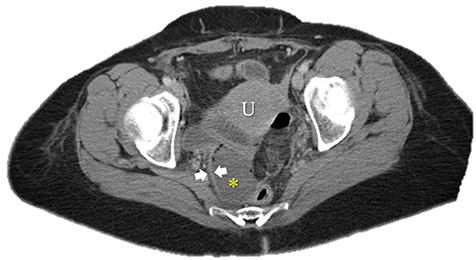

Immediate postoperative course was uneventful until postoperative day (POD)-5 when she experienced multiple watery stools, diffuse abdominal pain, fever (102.6F) and leukocytosis (23000/UL). Clostridium difficile infection was ruled out with a negative stool toxin assay. Her abdominal exam remained nonspecific until POD-6 when she had bilious emesis. A computed tomography (CT) scan revealed perforated diverticulitis with pelvic abscess and multiple colonic diverticulitis with an associated small bowel obstruction (SBO) (Images 1–4). No prior history of diverticulitis was reported.

Small bowel obstruction showing air-fluid levels with transition point in the distal ileum. Blue arrows: small bowel obstruction with transition point in distal ileum.